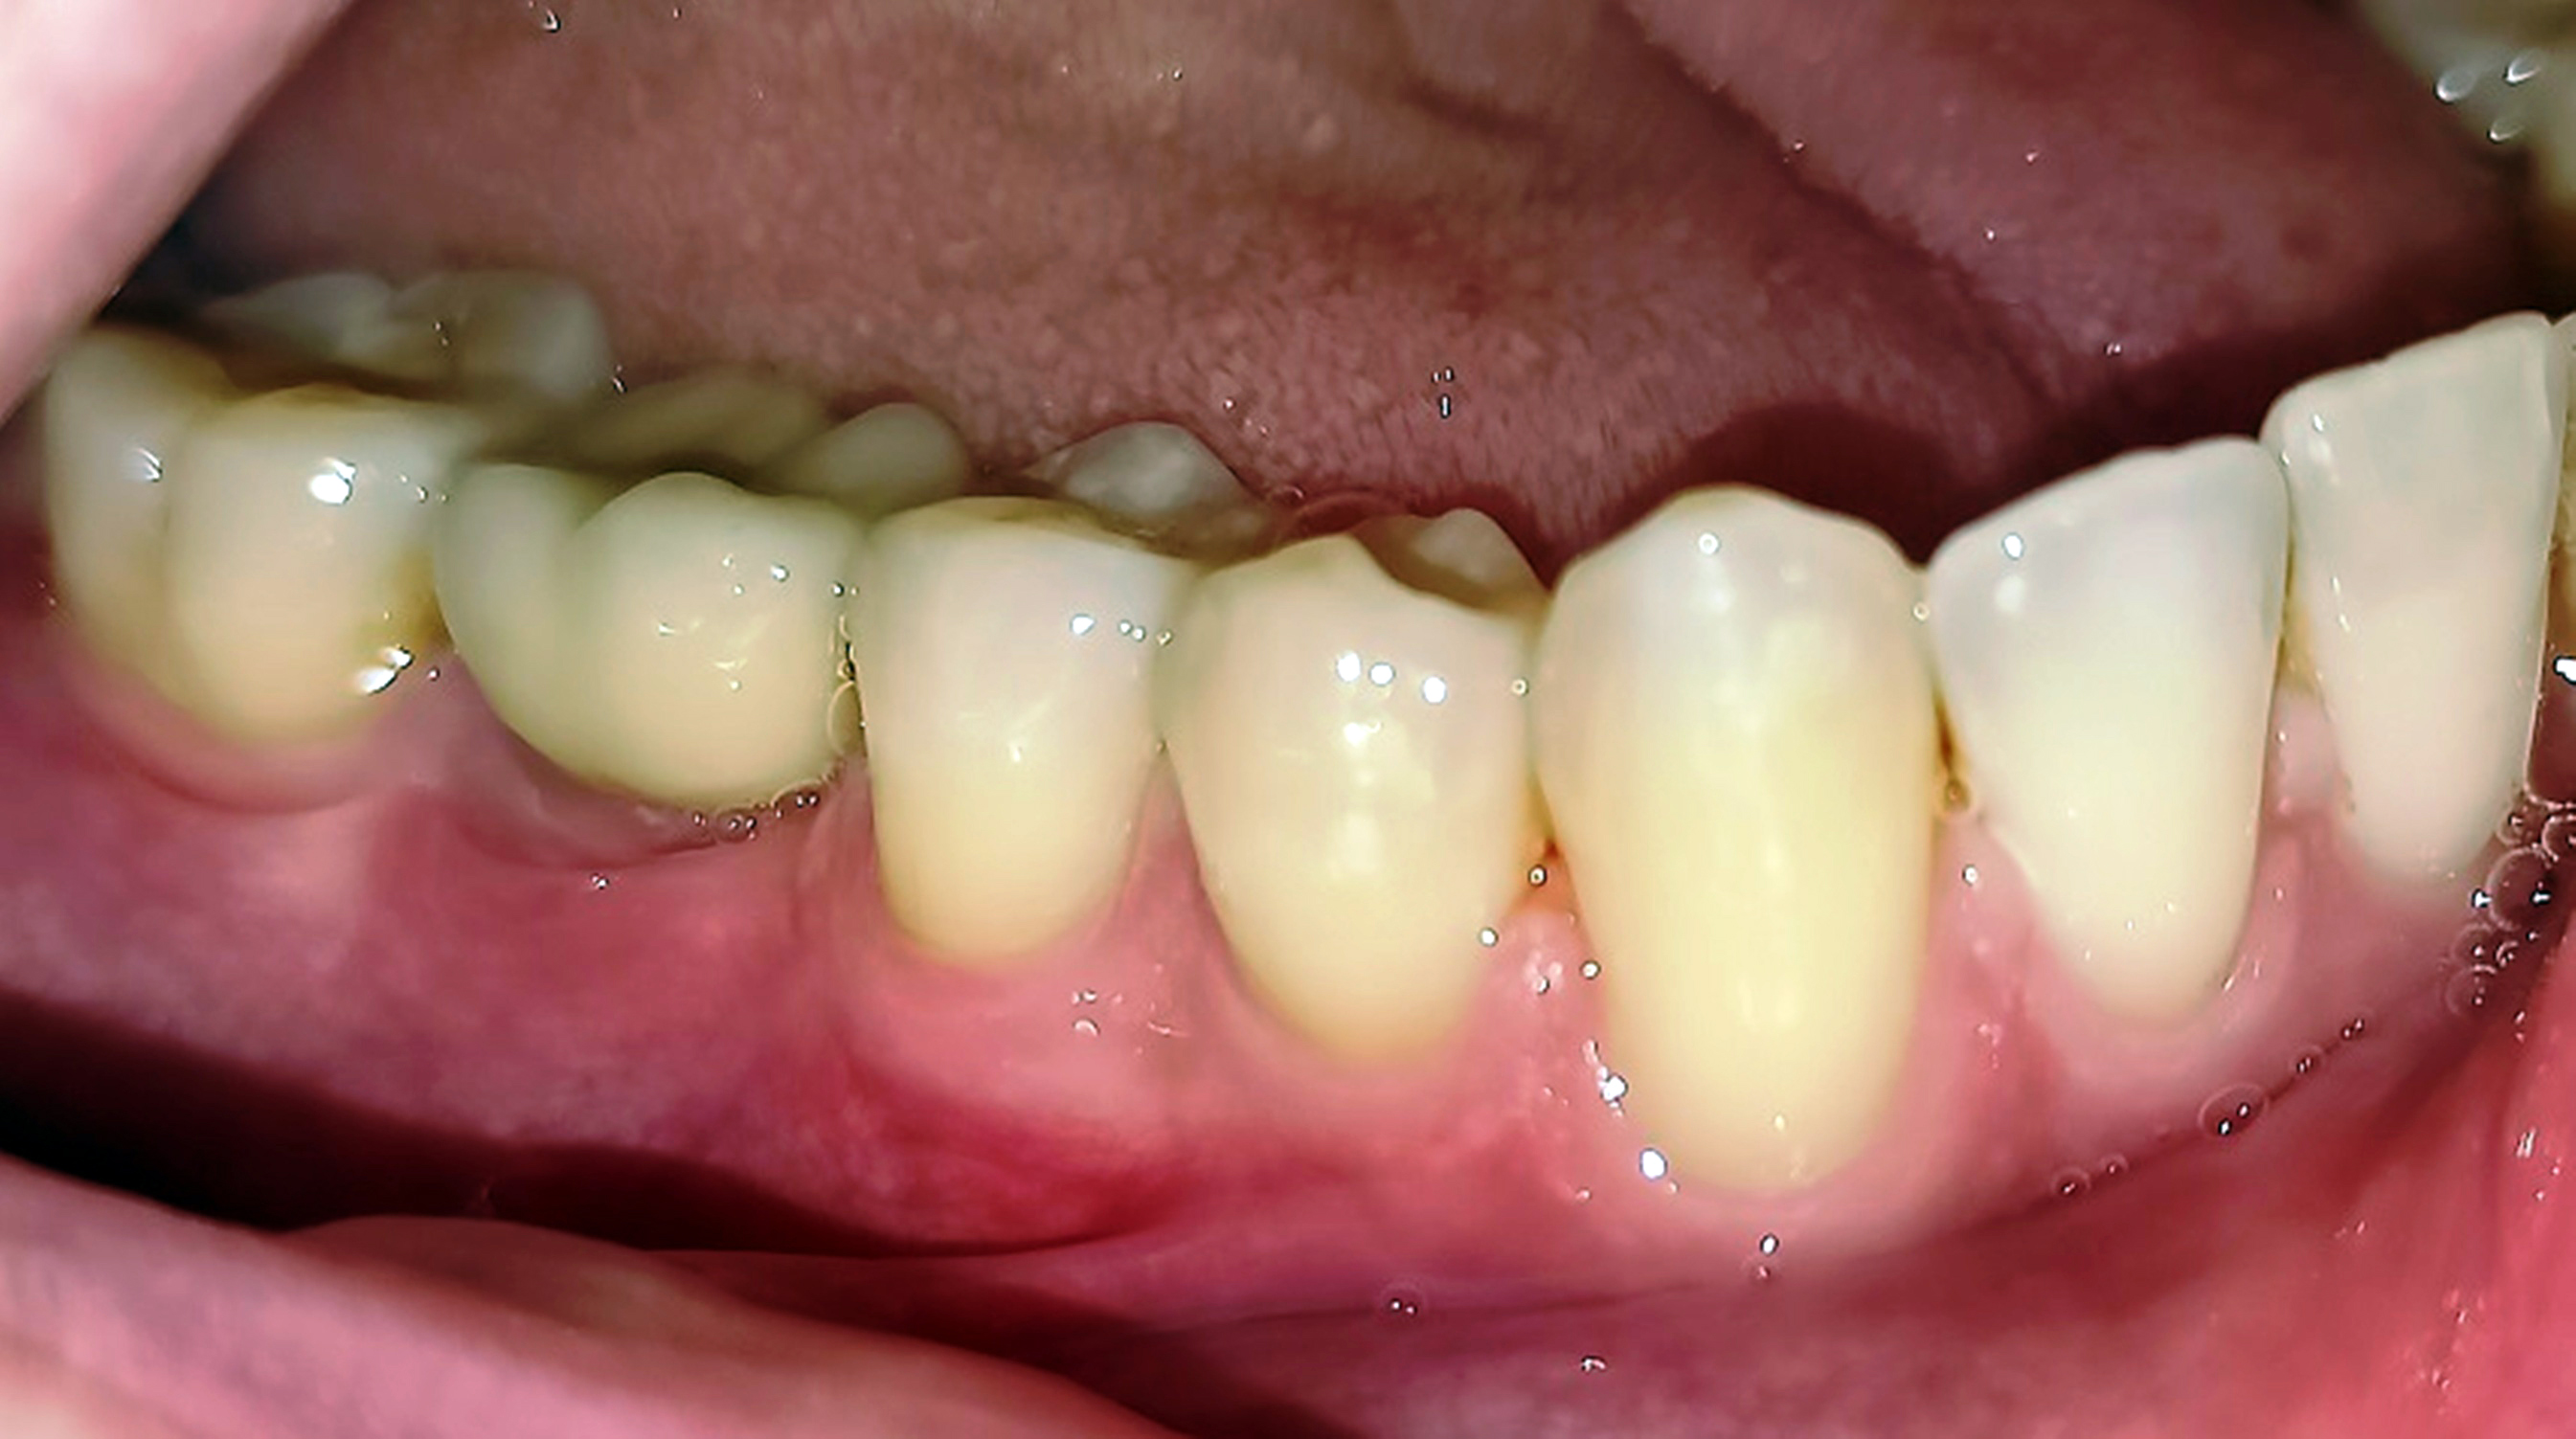

Innerhalb der Gruppe der Patienten mit Fazialisparese wurde außerdem ein Vergleich der Mundgesundheit zwischen beiden Mundhälften durchgeführt. Dabei wies die paretische Seite eine signifikant höhere Plaque-Kontamination, mehr Blutungen und höhere PSI-Werte auf als die nicht paretische Seite (Tab. 3). Die Plaque-Kontamination war in Bezug auf den API auf der paretischen Seite um 10,9 % (p = 0,004) höher als auf der nicht paretischen Seite. Ebenso wiesen die vestibulären Zahnoberflächen der paretischen Seite mehr Biofilm auf als die der nicht paretischen Seite (p = 0,002; s. Tab. 3, Abb. 2a und b). Dabei war der Unterschied bei den männlichen Patienten (0,8 vs. 0,5; p = 0,001) größer als bei den weiblichen Patienten (0,6 vs. 0,4; p = 0,002). Außerdem wurde bei Patienten mit rechtsseitiger Fazialisparese ein größerer Seitenunterschied (0,7 vs. 0,5; p < 0,001) dokumentiert als bei Patienten mit linksseitiger Fazialisparese (0,5 vs. 0,4; p = 0,043). Ursächlich erschien die Händigkeit der Patienten. Während bei Patienten mit linksseitiger Fazialisparese die Erkrankung auf der für Rechtshänder besser zu reinigenden Mundhälfte vorlag, waren rechtshändige Patienten mit rechtsseitiger Fazialisparese einer doppelten Belastung ausgesetzt (18). Die Gingivablutung nach Sondierung war auf der paretischen Seite ebenfalls signifikant höher als auf der nicht paretischen Seite (s. Tab. 3). Das spiegelte sich sowohl bei den Werten des SBI (s. Tab. 3, Abb. 3) als auch bei den Werten des PBI (s. Tab. 3, Abb. 4a und b) wider. Die Sondierungstiefen waren auf der paretischen Seite im Vergleich zur nicht paretischen Seite tiefer und der Attachmentverlust war höher. Dabei konnte jedoch kein signifikanter Unterschied nachgewiesen werden. Der mittlere PSI erreichte auf der paretischen Seite signifikant höhere Werte als auf der nicht paretischen Seite (p = 0,032; s. Tab. 3), was auf eine schlechtere Gingivagesundheit hinweist. Darüber hinaus war die Prävalenz unbehandelter kariöser Läsionen auf der paretischen Seite höher als auf der nicht paretischen Seite (s. Tab. 3). Ein Fallbeispiel illustriert eindrucksvoll die Unterschiede zwischen der kariesfreien nicht paretischen Seite und der paretischen Seite mit multiplen aktiv kariösen Läsionen (Abb. 5a und b). Zusätzlich wies die paretische Seite eine höhere Anzahl an Restaurationen auf als die nicht paretische Seite (s. Tab. 3). Hinsichtlich des Zahnsteinbefalls wurden auch im Seitenvergleich der Mundhälften keine signifikanten Unterschiede zwischen den paretischen und den nicht paretischen Seiten festgestellt. Im Einzelfall wurden jedoch eindrucksvolle Unterschiede zwischen den Mundhälften deutlich (Abb. 6a und b).